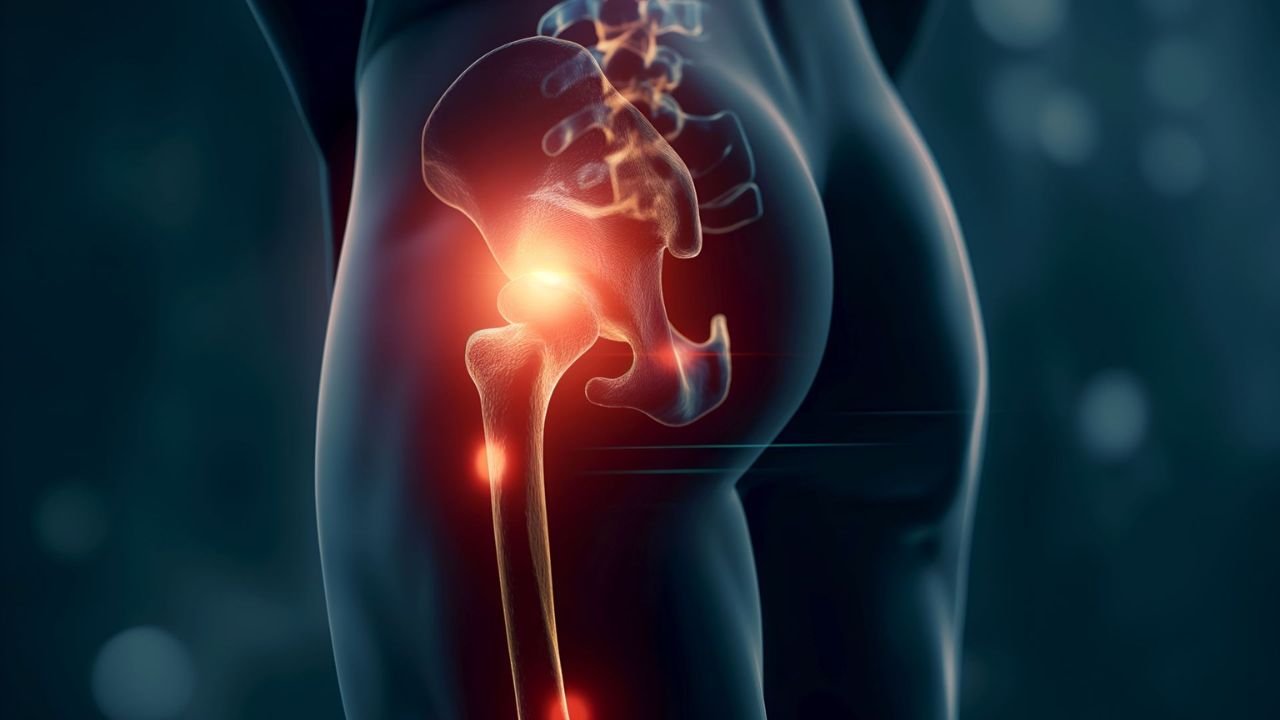

Dor na Articulação Sacroilíaca

A sacroileíte é uma inflamação na articulação sacroilíaca, que conecta a base da coluna vertebral (sacro) à bacia (ílio). Essa

A sacroileíte é uma inflamação na articulação sacroilíaca, que conecta a base da coluna vertebral (sacro) à bacia (ílio). Essa

A sacroileíte é uma inflamação na articulação sacroilíaca, que conecta a base da coluna vertebral (sacro) à bacia (ílio). Essa

A sacroileíte é uma inflamação na articulação sacroilíaca, que conecta a base da coluna vertebral (sacro) à bacia (ílio). Essa